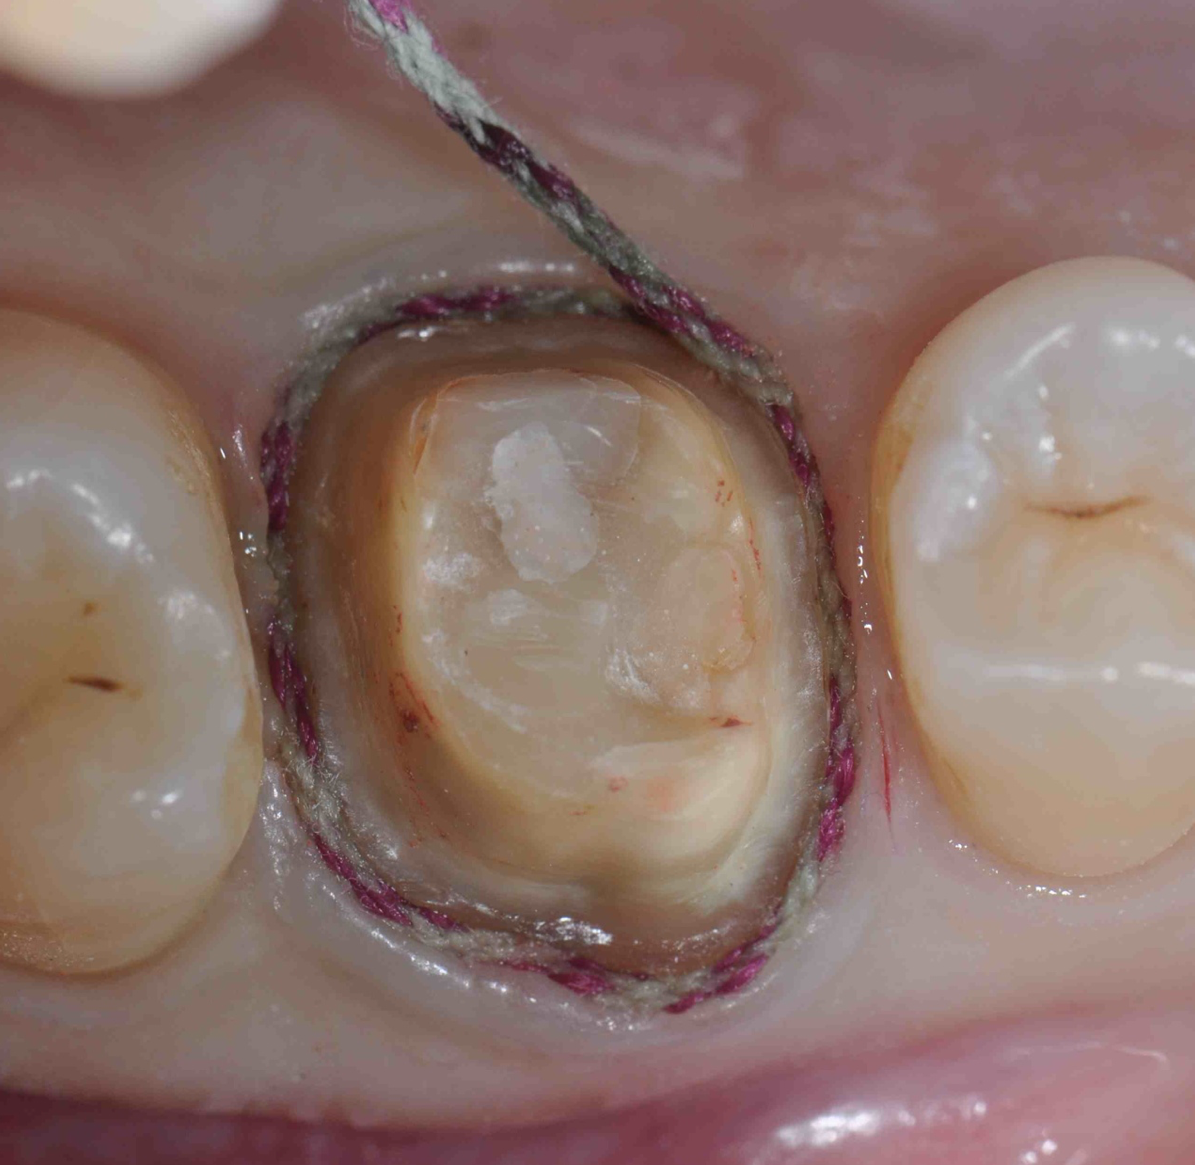

Figure 3: Retraction cord placed for a single-unit crown preparation. Note the 360ยบ visibility of the cord.

Figure 3

Figure 4: Impression made of the tooth in Figure 3. Note the flash is consistently 1-mm deep and 1-mm wide, reflecting the precise placement of the retraction cord prior to the impression.

Figure 4

Retraction cords are available with and without vasoconstrictors; the author prefers stiffer ones and using the two-cord method described below. They are usually placed completely around the prepared tooth and placed at the top of the sulcus, so the entire diameter of the cord is visible and the clinician can ascertain that the flash of the light-body material will have the desired 1-mm depth and 1-mm thickness (Figure 3 and Figure 4). If placed too deeply in the sulcus, the tissue can partially cover the cord and prevent the light-body material from correctly recording a correct impression.